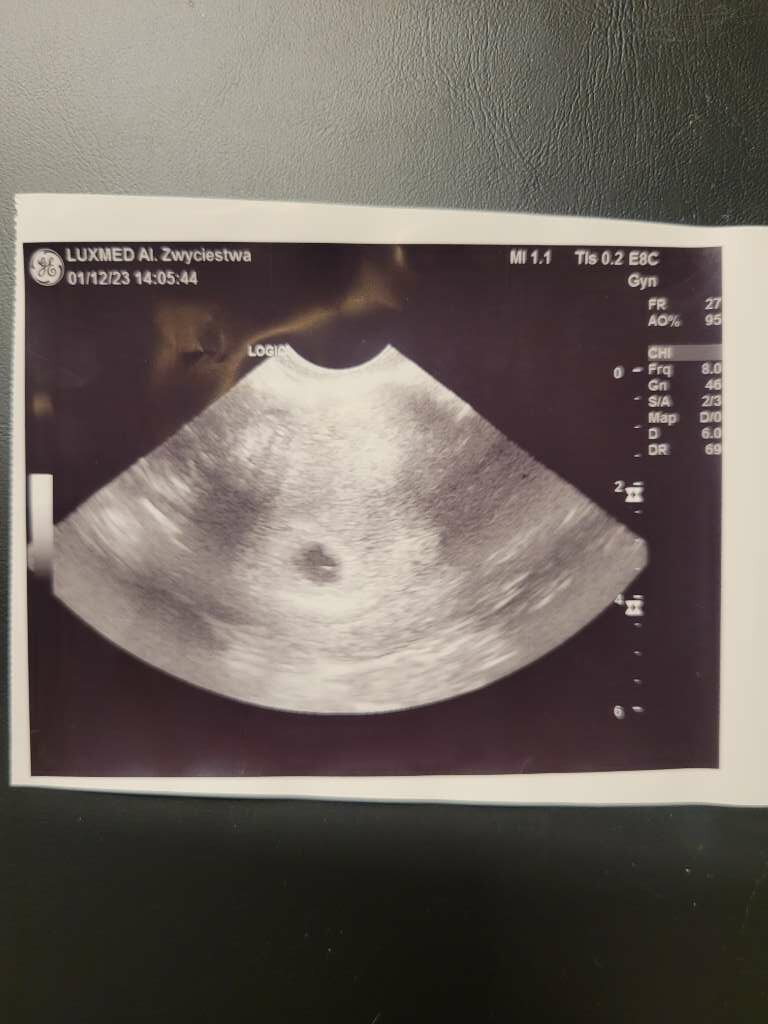

Natomiast wczoraj zestresował mnie lekarz z luxmedu... to było 5+4 i zobaczyl pęcherzyk... zapytam tylko czy widzi to co.powinien na tym etapie na co.on, że nie... bo to 6 tydzien i.powinien być już zarodek.

Wyszłam z przekonaniem, że pewnie skończy się jak.poprzednio... z tego stresu nie zapytalam .nawet czy jest pęcherzyk zóltkowy, chciałam tylko wyjsc i chciało mi sie ryczeć mimo, że ja z tym "twardych"... (mam zdjecie ale nie znam się) jestem zdołowana i chyba szukam wsparcia... by ktoś powiedział, że na tym etapie ciąży również nie ma jeszcze zarodka...